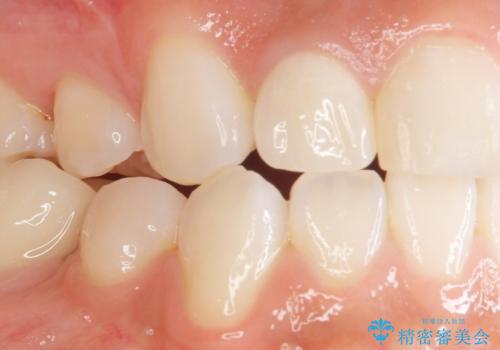

- 上の前歯の色と隙間を気にされ、来院された患者様です。

精査したところ、右上の側切歯(右上2)は神経が死んで変色しており、左上の側切歯と犬歯の間に2mm程度の隙間を認めました。

矯正せずに早く治したいという強いご希望により、セラミッククラウンによる補綴治療(上顎両側2の2本)を行いました。

天然歯のような自然な仕上がりに大変喜んで頂けました。

クラウンの種類:オールセラミッククラウン スペシャル